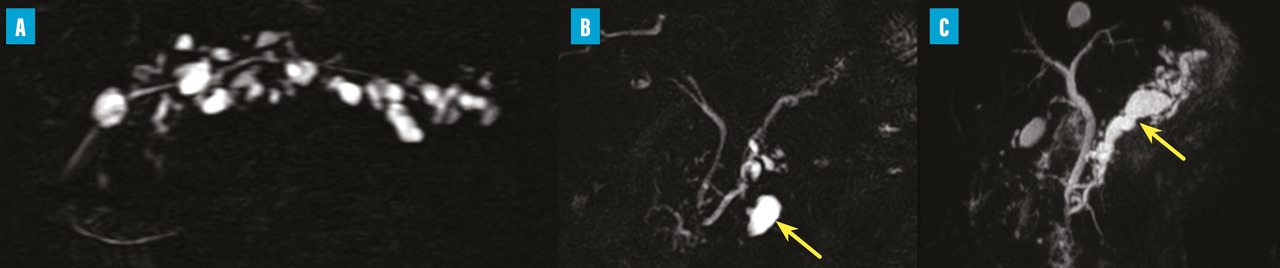

Les TIPMP sont des lésions canalaires intra-épithéliales développées aux dépens des canaux pancréatiques (principal ou/et secondaires) [fig. 1]. Elles prédominent au niveau de la tête et du crochet, mais peuvent concerner toute la glande. La composante kystique des TIPMP présente un épithélium de type mucineux avec production de mucus. Au cours du processus d’oncogenèse, des papilles commencent à se former, et différents phénotypes cellulaires distincts ont été décrits, corrélés à leur pronostic.

Les tumeurs kystiques mucineuses (TKM) sont des lésions précancéreuses bordées par un revêtement épithélial, sécrétant de la mucine. Il est caractéristique de trouver un stroma de type ovarien, positif en immunohistochimie à la progestérone. Le sex-ratio est fortement en faveur des femmes  : (20 femmes pour 1 homme). La découverte est principalement fortuite ou plus rarement sur pancréatite aiguë. Il s’agit d’une lésion unique, macrokystique, sans communication avec les canaux pancréatiques. Elle se situe quasi exclusivement au niveau de la face postérieure du corps et de la queue du pancréas (fig. 3). La lésion est uni- ou multiloculaire, limitée, hypodense, avec rehaussement de la paroi. Il existe de possibles nodules muraux, calcifications périphériques ou cloisons internes.

Il s’agit d’une tumeur kystique multiloculaire pouvant mesurer de 1 à plus de 20 cm, avec un aspect de «  cicatrice  » fibreuse centrale, parfois calcifiée (fig. 4). Ils sont plus fréquents chez les femmes (3 femmes pour 1 homme) avec un âge médian au diag­nostic autour de 60 ans. Ils sont le plus souvent de découverte fortuite ou secondaire à l’exploration de douleurs abdominales aspécifiques. Leur taille est stable dans le temps dans 60 % des cas, ou avec une croissance lente (4 mm/an). Les complications sont rares, et la dégénérescence exceptionnelle (moins de dix cas décrits dans la littérature), la surveillance n’est donc pas nécessaire. Pour les exceptionnelles lésions volumineuses (10 % de séreux macrokystiques), une chirurgie peut se discuter12 si elles sont à l’origine de symptômes invalidants.